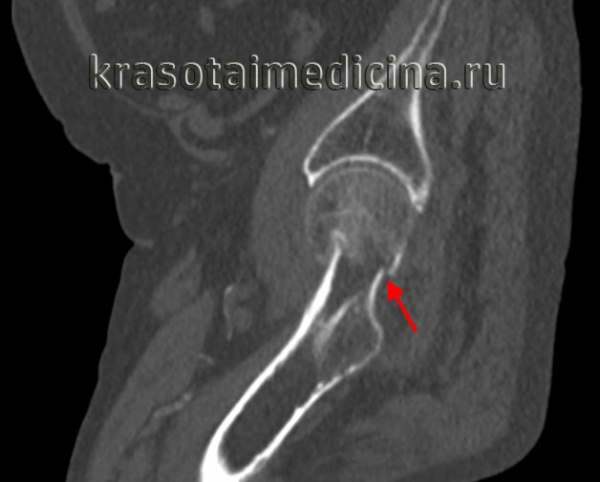

Класс А: перелом головки бедренной кости

Перелом головки бедренной кости встречается редко и может проявиться в сочетании с вывихом или без какой-либо значительной деформации. Его классифицируют по двум типам на основании размера и количества фрагментов. При переломах I типа имеется один фрагмент, в то время как переломы II типа являются оскольчатыми.

Для выявления этих переломов достаточно снимков тазобедренного сустава в обычных проекциях.